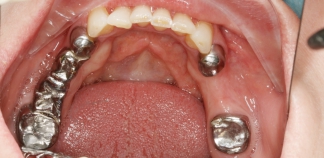

До лечения

Пациент обратился с просьбой заменить съемные протезы на несъемные.

Как лечили

Проведено протезирование по протоколу «All-on-4» на верхней челюсти и съемное протезирование на двух имплантах на нижней челюсти.

Лечащие врачи

МАРКОСЯН Геворк Сандроевич, ТИГРАНЯН Варангюл Гургенович